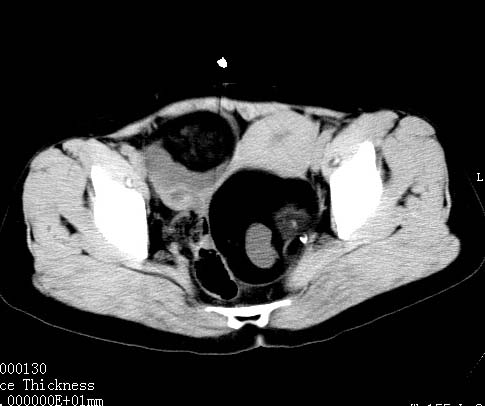

女性 病人 44岁 盆腔 下腹部痛1天!

盆腔内低密度为主混杂等密度及少许囊样与班状钙化影,如果做了肠道准备就好了。支持畸胎瘤。当然做mri会更好

典型的双侧附件畸胎瘤.

支持各位大侠观点.病人有急性腹痛,需除外有扭转可能.建议mri.